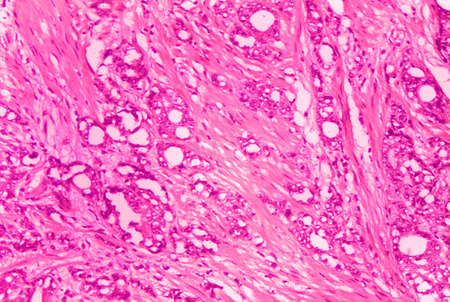

Breast cancer of the woman diseased tissue 100x